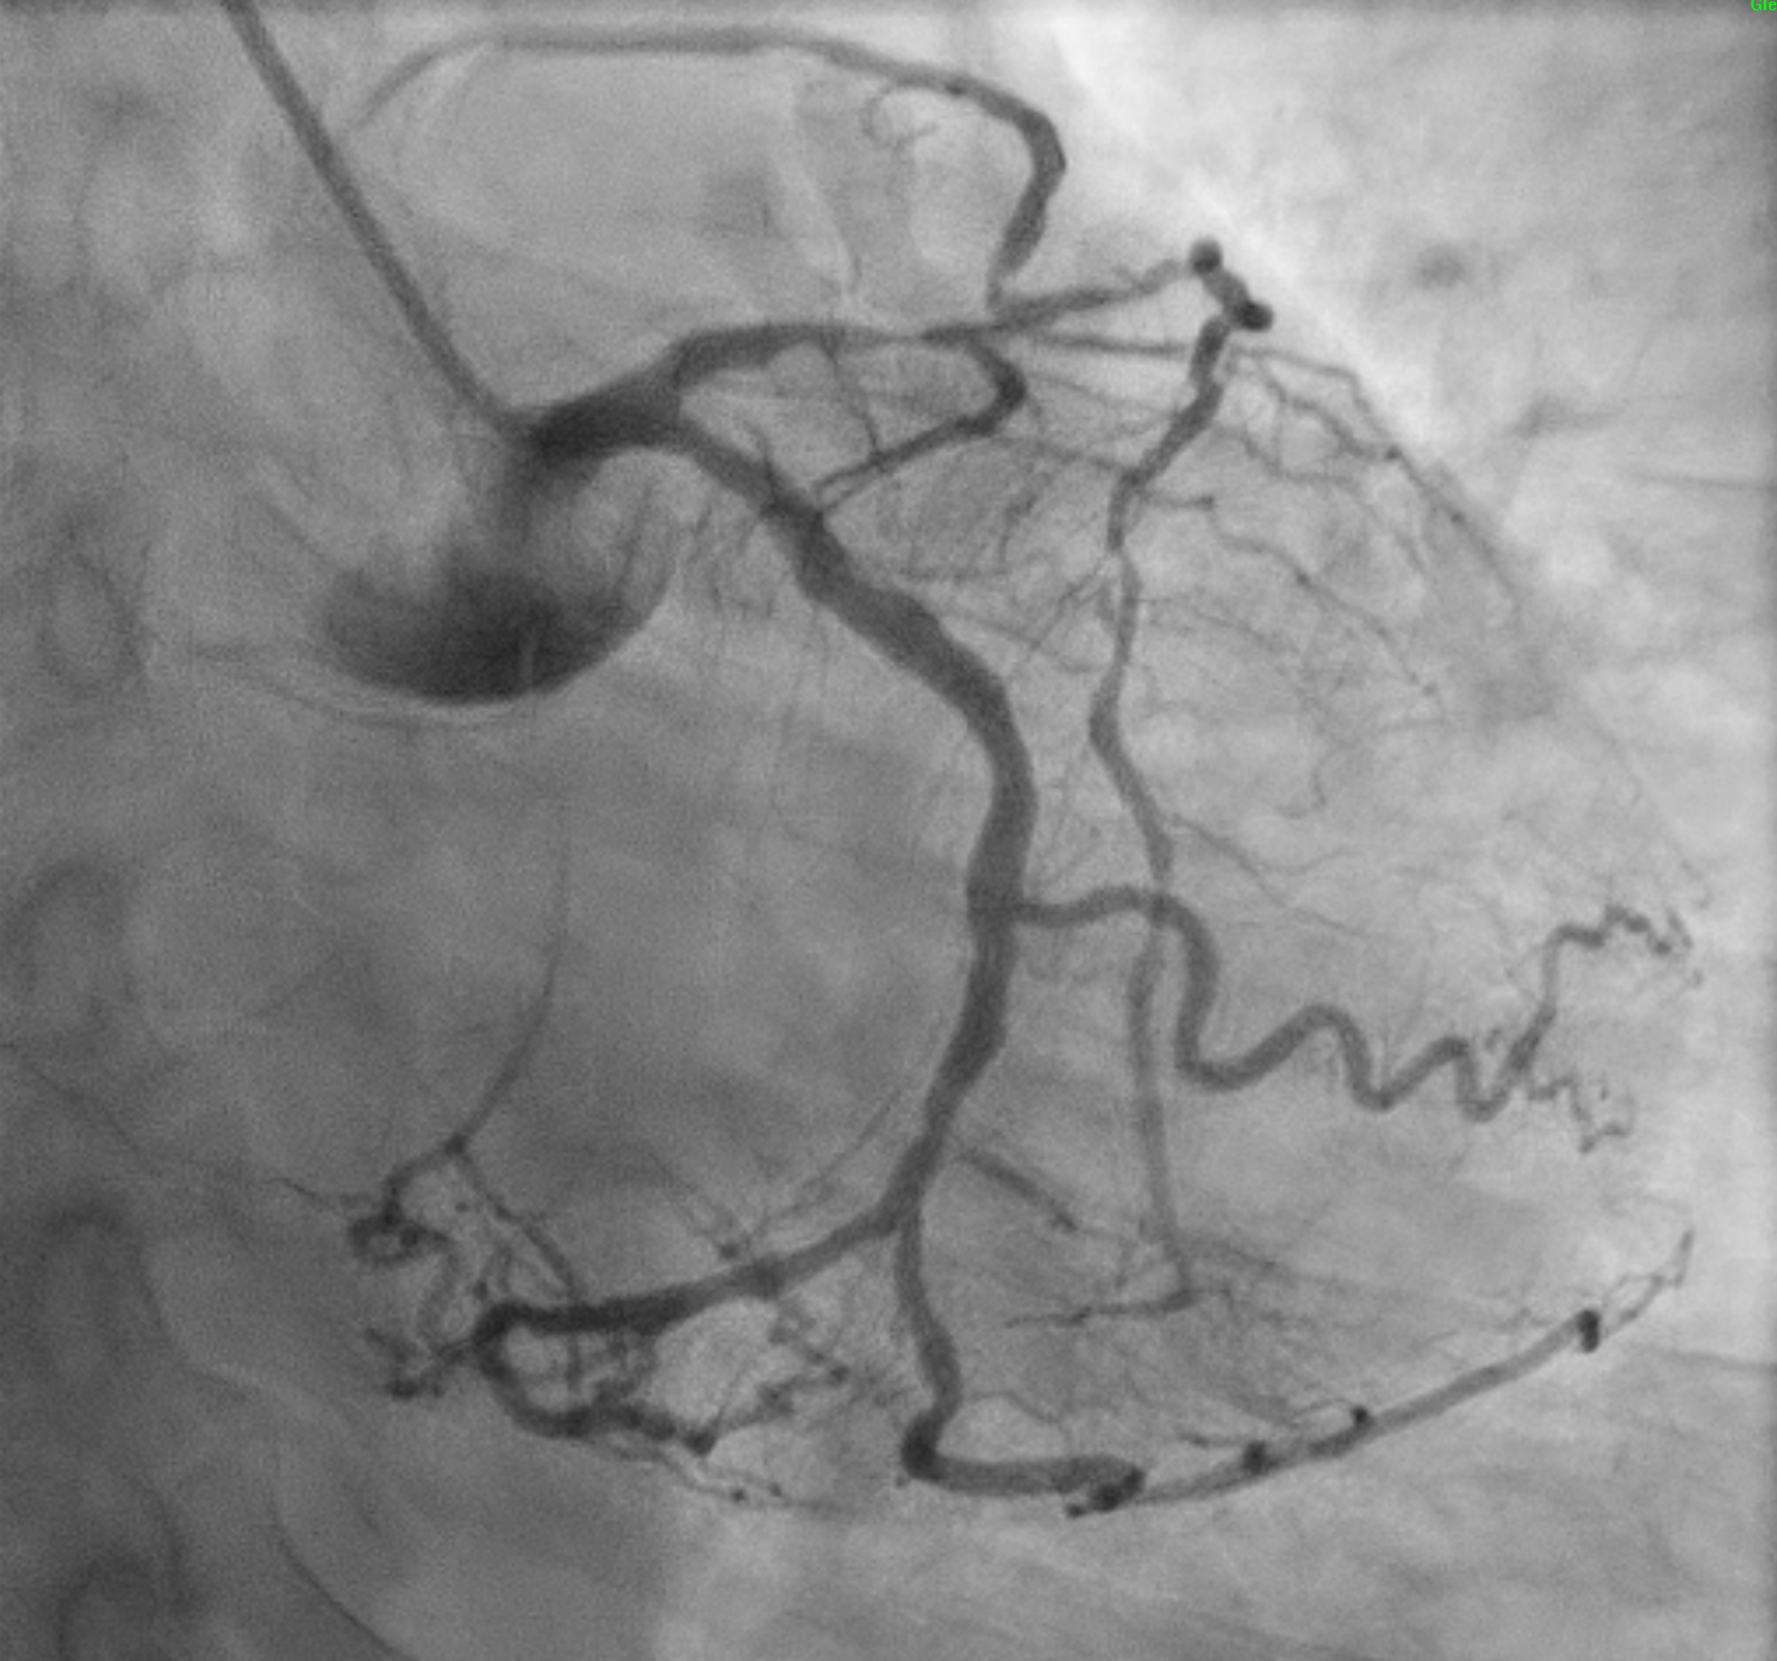

The initial angiogram on July 3rd, 2025, showed two-vessel coronary artery disease, with diffuse atherosclerosis extending from the proximal to distal LAD and moderate stenosis of the OM2. The RCA was absent and appeared to be supplied by the D1 branch, which showed severe disease at the ostium and mid segment. A repeat angiogram showed drop of blood flow with TIMI 2 flow to the distal LAD and RCAterritories. Then we proceed to PCI to LAD and RCA.

An IVUS-guided PCI of the LAD and RCA was performed via right radial access. An EBU 3.5, 7 Fr guiding catheter engaged the left main, and a Sion Blue wire was advanced to the distal LAD for pre-dilatation with a 2.5 mm NC balloon. Wiring the anomalous RCA from the LAD was challenging due to a retroflexed ostium but was achieved using a reverse wire technique with adual-lumen (Sasuke) catheter and Sion Black wire. Difficulty crossing the mid RCA, likely due to dissection, required multiple wire exchanges before reaching the distal RCA. Lesion preparation used 2.0 mm and 1.5 mm NC balloons in the RCA. IVUS showed LAD diameters of 2.5mm distally with diffuse disease and < 40%plaque burden. A hybrid revascularization strategy was planned. Further preparation involved 3.0 mm and 2.0 mm balloons in the LAD and RCA. DCBs (2.0 ¡¿25 mm in distal LAD; 2.0 ¡¿ 20 mm in RCA) were applied for 60 seconds each. A Xience Sierra 3.0 ¡¿ 38 mm DES was deployed in the proximal–mid LAD,post-dilated with 3.0–3.5 mm NC balloons and optimized with a 4.0 mm POT. IVUS revealed a distal edge dissection, covered with an additional overlapping Xience Sierra 2.75 ¡¿ 23 mm DES. Final IVUS confirmed good stent expansion (MSA6 mm©÷), and angiography showed non–flow-limiting distal LAD dissection with TIMI 3 flow in both LAD and RCA.